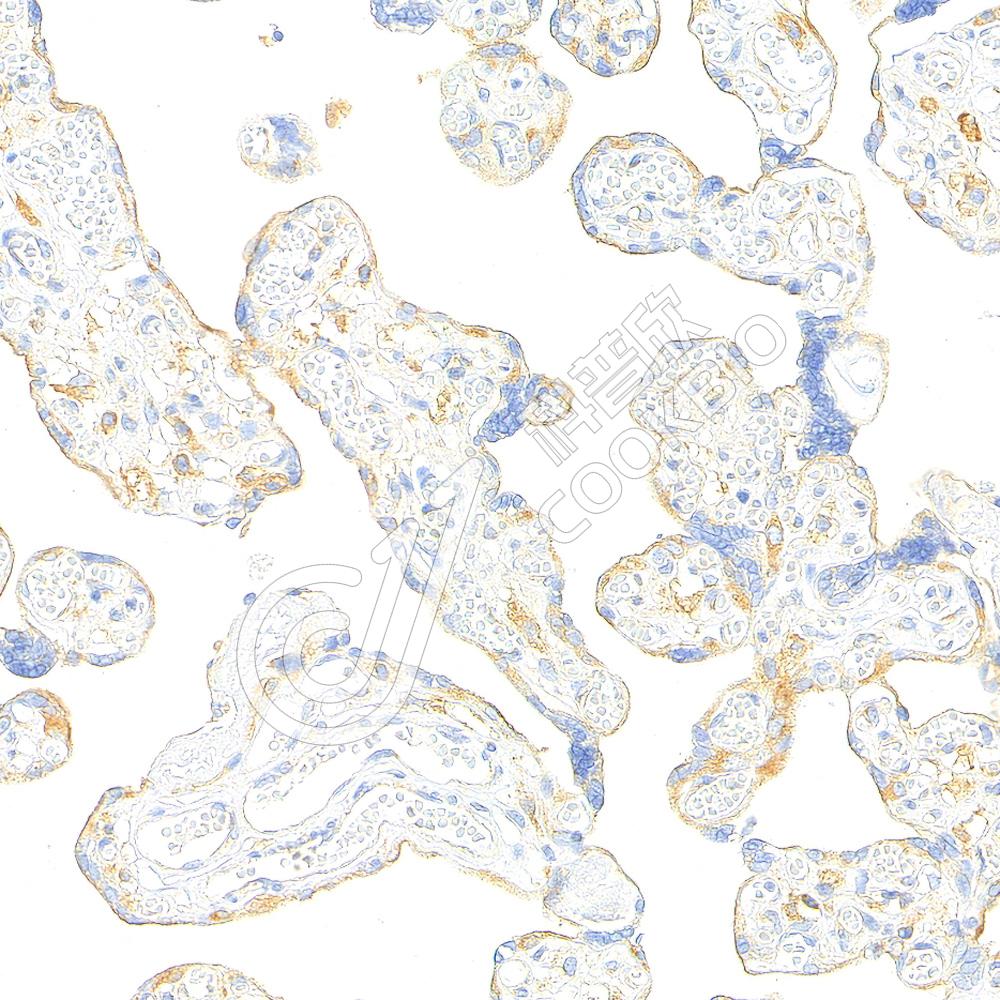

IHC检测Myeloperoxidase蛋白(货号 K2360048).

样品: 人扁桃体, 4%多聚甲醛 (货号KSG1101) 固定12-24小时.

抗原修复: 柠檬酸抗原修复液(干粉, pH 6.0) (KSG1201), 高压锅均匀喷气计时2分钟.

—抗: 1: 1000稀释, 4℃ 孵育过夜.

二抗: S-vision免疫组化多聚二抗(山羊抗小鼠), 即用型(货号KB3903), 室温孵育20分钟.